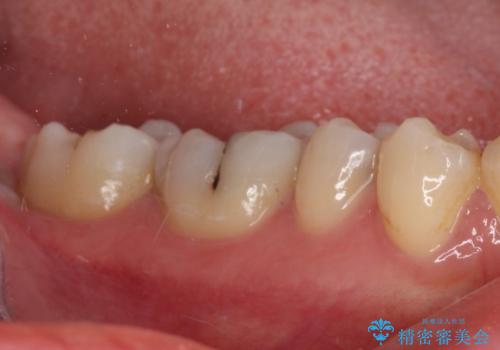

速やかにラバーダム下にて根管治療を行うこととし、その後オールセラミッククラウンにて補綴治療を行うこととしました。

治療期間中、痛みが生じることはなく、処置後3か月経過しましたが良好な状態を保っています。